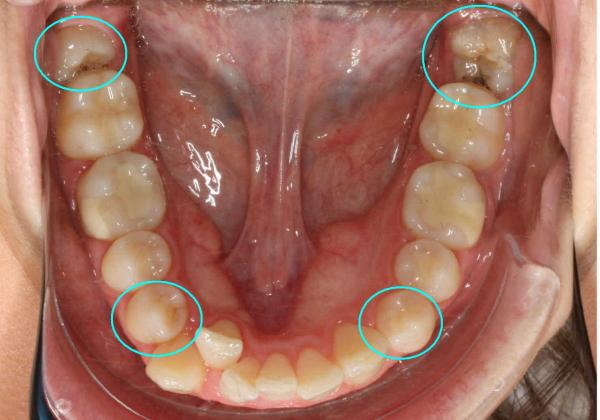

Последствия удаления ретинированного зуба мудрости

Если зуб мудрости прорезался не полностью, или его положение неверно по отношению к другим зубам (восьмёрка может расти в щёку или в соседний зуб), его называют ретинированным зубом. В таком случае операция по удалению может оказаться особенно сложной, и иметь неприятные последствия:

Фото 3. На фото видны изменения, к которым привели зубы мудрости, при этом остальные начали сдвигаться, торчать в разные стороны.

Фото 4. На фото видно, что нижние зубы мудрости растут в неправильном положении, в такой ситуации один из резцов ушел внутрь челюсти.